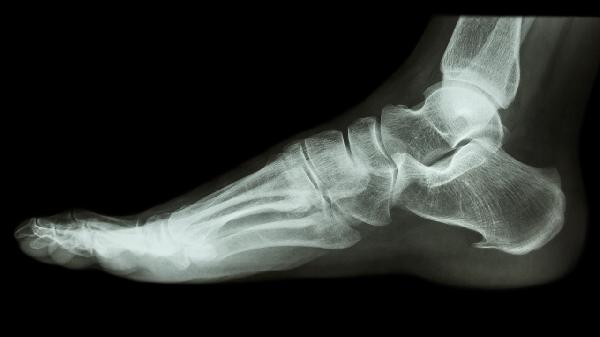

足跟骨质增生疼痛可通过热敷理疗、药物镇痛、足弓支撑、适度运动及中医治疗等方式缓解。骨质增生通常由长期劳损、退行性变、足部畸形、炎症刺激或代谢异常等因素引起。

定制矫形鞋垫可纠正足部力线异常,减轻跟骨受力。选择后跟杯加厚的运动鞋,避免穿平底鞋或高跟鞋。夜间使用足踝支具保持足部中立位,防止晨起时足底筋膜紧张。

建议控制体重减轻足部负荷,每日钙摄入量维持在800-1000毫克,补充维生素D促进钙吸收。避免长时间站立行走,每1小时休息5分钟。疼痛持续加重或出现足跟明显变形时,需及时就医评估是否需手术治疗。睡眠时抬高下肢促进静脉回流,晨起前可先做足部背屈活动再下床。